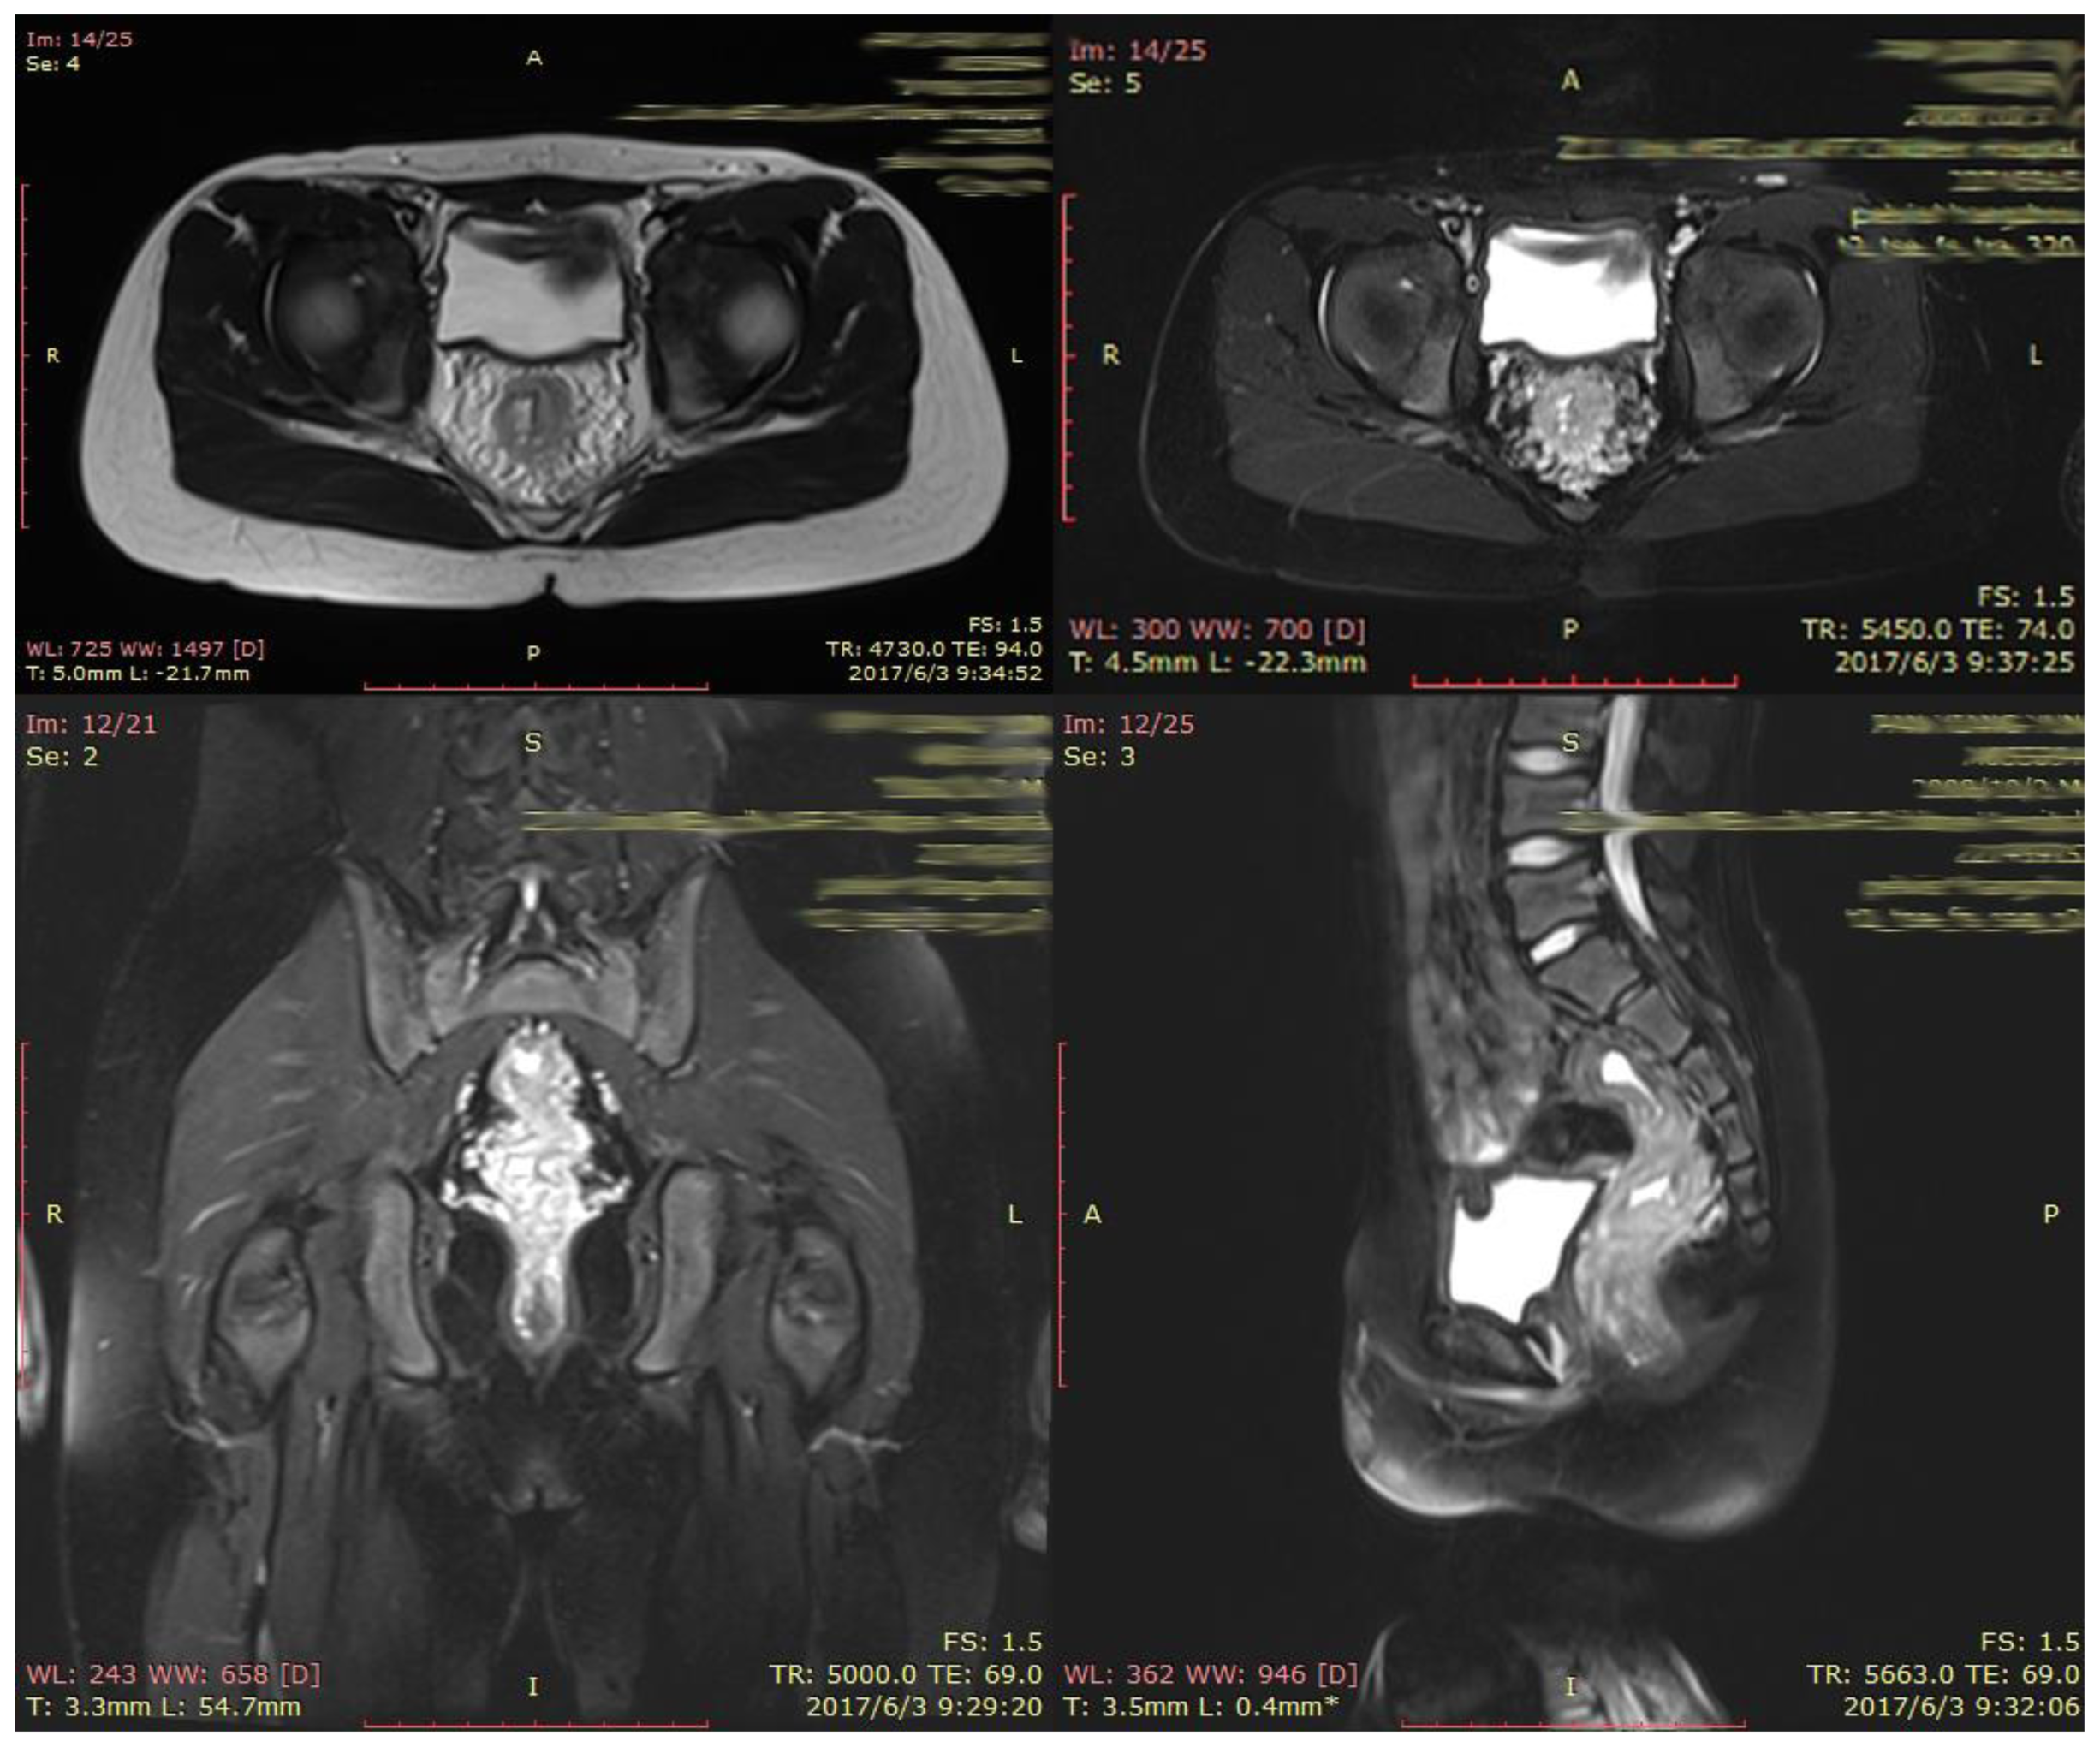

2. CASE PRESENTATION